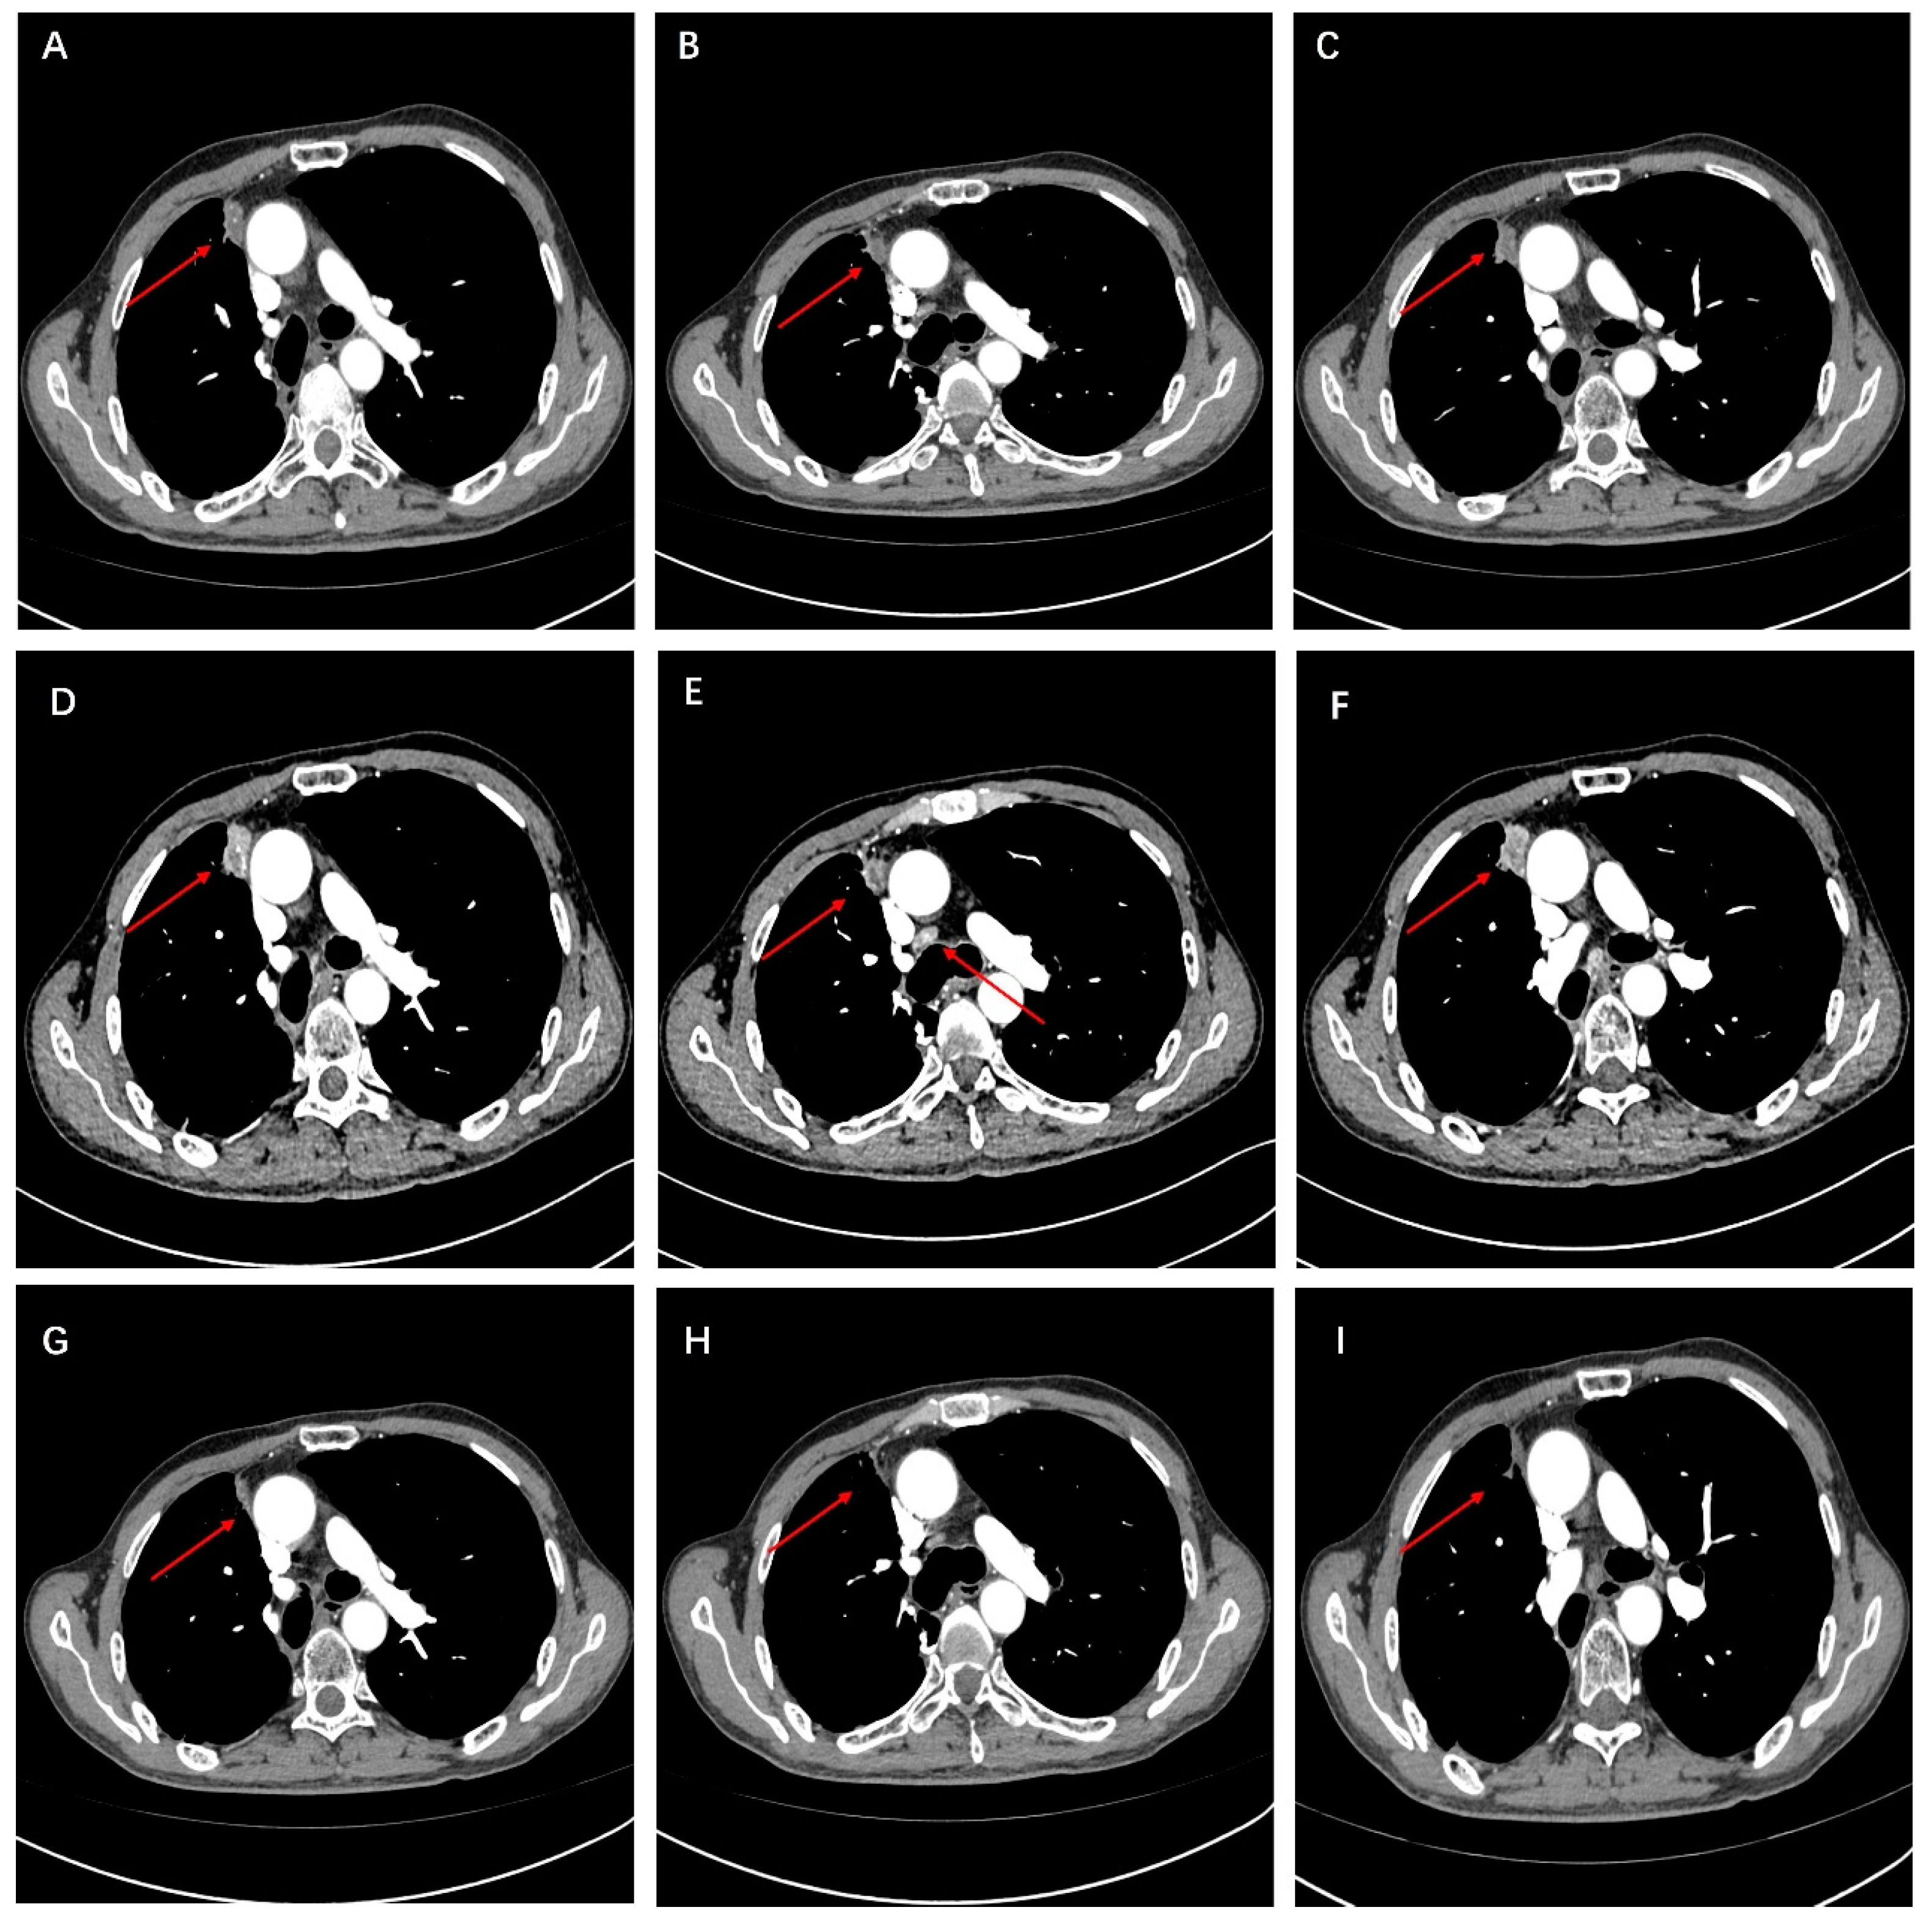

2. Case Presentation